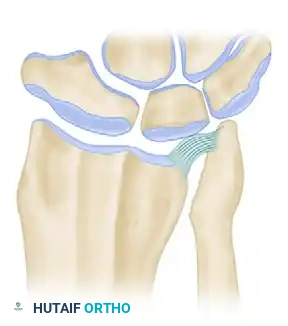

Figure 2: The ulnar head is resected to resemble a tapering dowel, meticulously preserving the ulnar styloid and the critical attachments of the TFCC.

Figure 3 (Bowers A): Demonstration of impingement. Because the ulna is too long relative to the resection, the remaining ulnar shaft impinges on the stylocarpal ligament and the radius during rotation and ulnar deviation.